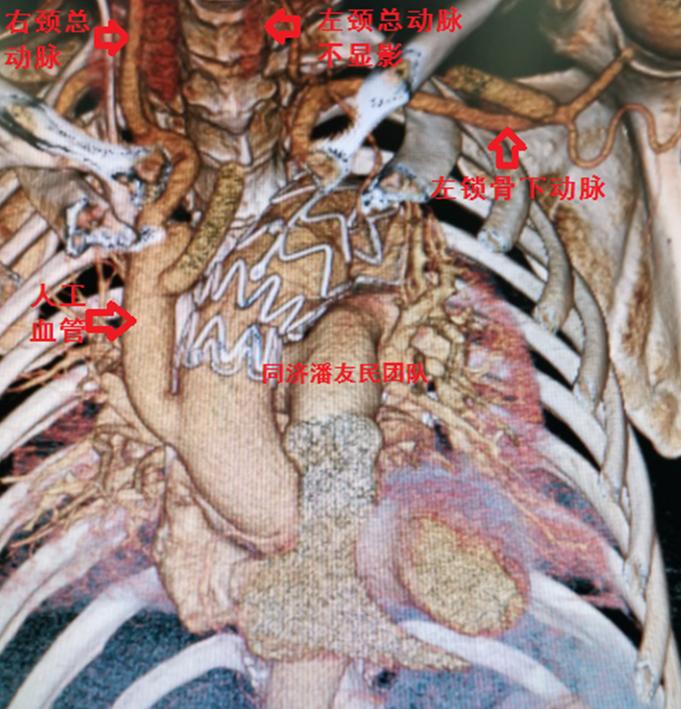

出院前复查主动脉CTA(图10)显示杂交手术重建弓部分支血管正常(左颈总动脉仍不显影)。